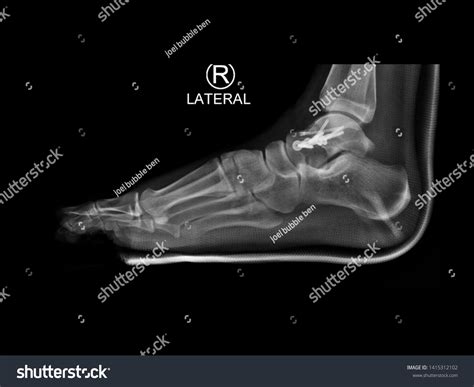

A Lateral Foot X Ray is a type of radiographic imaging that captures a side view of the foot. This view is essential for evaluating the alignment and integrity of the bones, joints, and soft tissues in the foot. Unlike an anteroposterior (AP) view, which provides a front-to-back image, a lateral view offers a different perspective that can reveal issues not visible in other projections.

Obtaining a lateral foot X ray is a straightforward process that typically involves the following steps:

• Patient Preparation: The patient is asked to remove any jewelry or metal objects from the foot area to avoid interference with the X-ray image.

• Positioning: The patient stands or sits with the foot placed on a platform. The foot is positioned at a 90-degree angle to the X-ray beam to ensure a true lateral view.

• Imaging: The radiographer takes the X-ray, and the image is captured on a digital detector or film.

• Review: The radiologist reviews the image to ensure it is of diagnostic quality and interprets the findings.

Interpreting a Lateral Foot X Ray

Interpreting a lateral foot X ray requires a trained eye and knowledge of foot anatomy. Here are some key points to consider:

• Bone Density: Assess the density and clarity of the bones. Abnormalities in bone density can indicate conditions like osteoporosis or bone tumors.

• Bone Alignment: Check the alignment of the bones, particularly the calcaneus, talus, and metatarsals. Misalignment can indicate fractures, dislocations, or deformities.

• Joint Spaces: Evaluate the joint spaces for any narrowing or irregularities, which can suggest arthritis or other joint diseases.

• Soft Tissue: Look for any abnormalities in the soft tissue, such as swelling, calcifications, or foreign bodies.